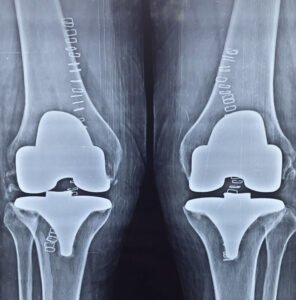

X-rays of patient of bilateral knee replacement in one sitting before and after surgery

Post Operation X-rays